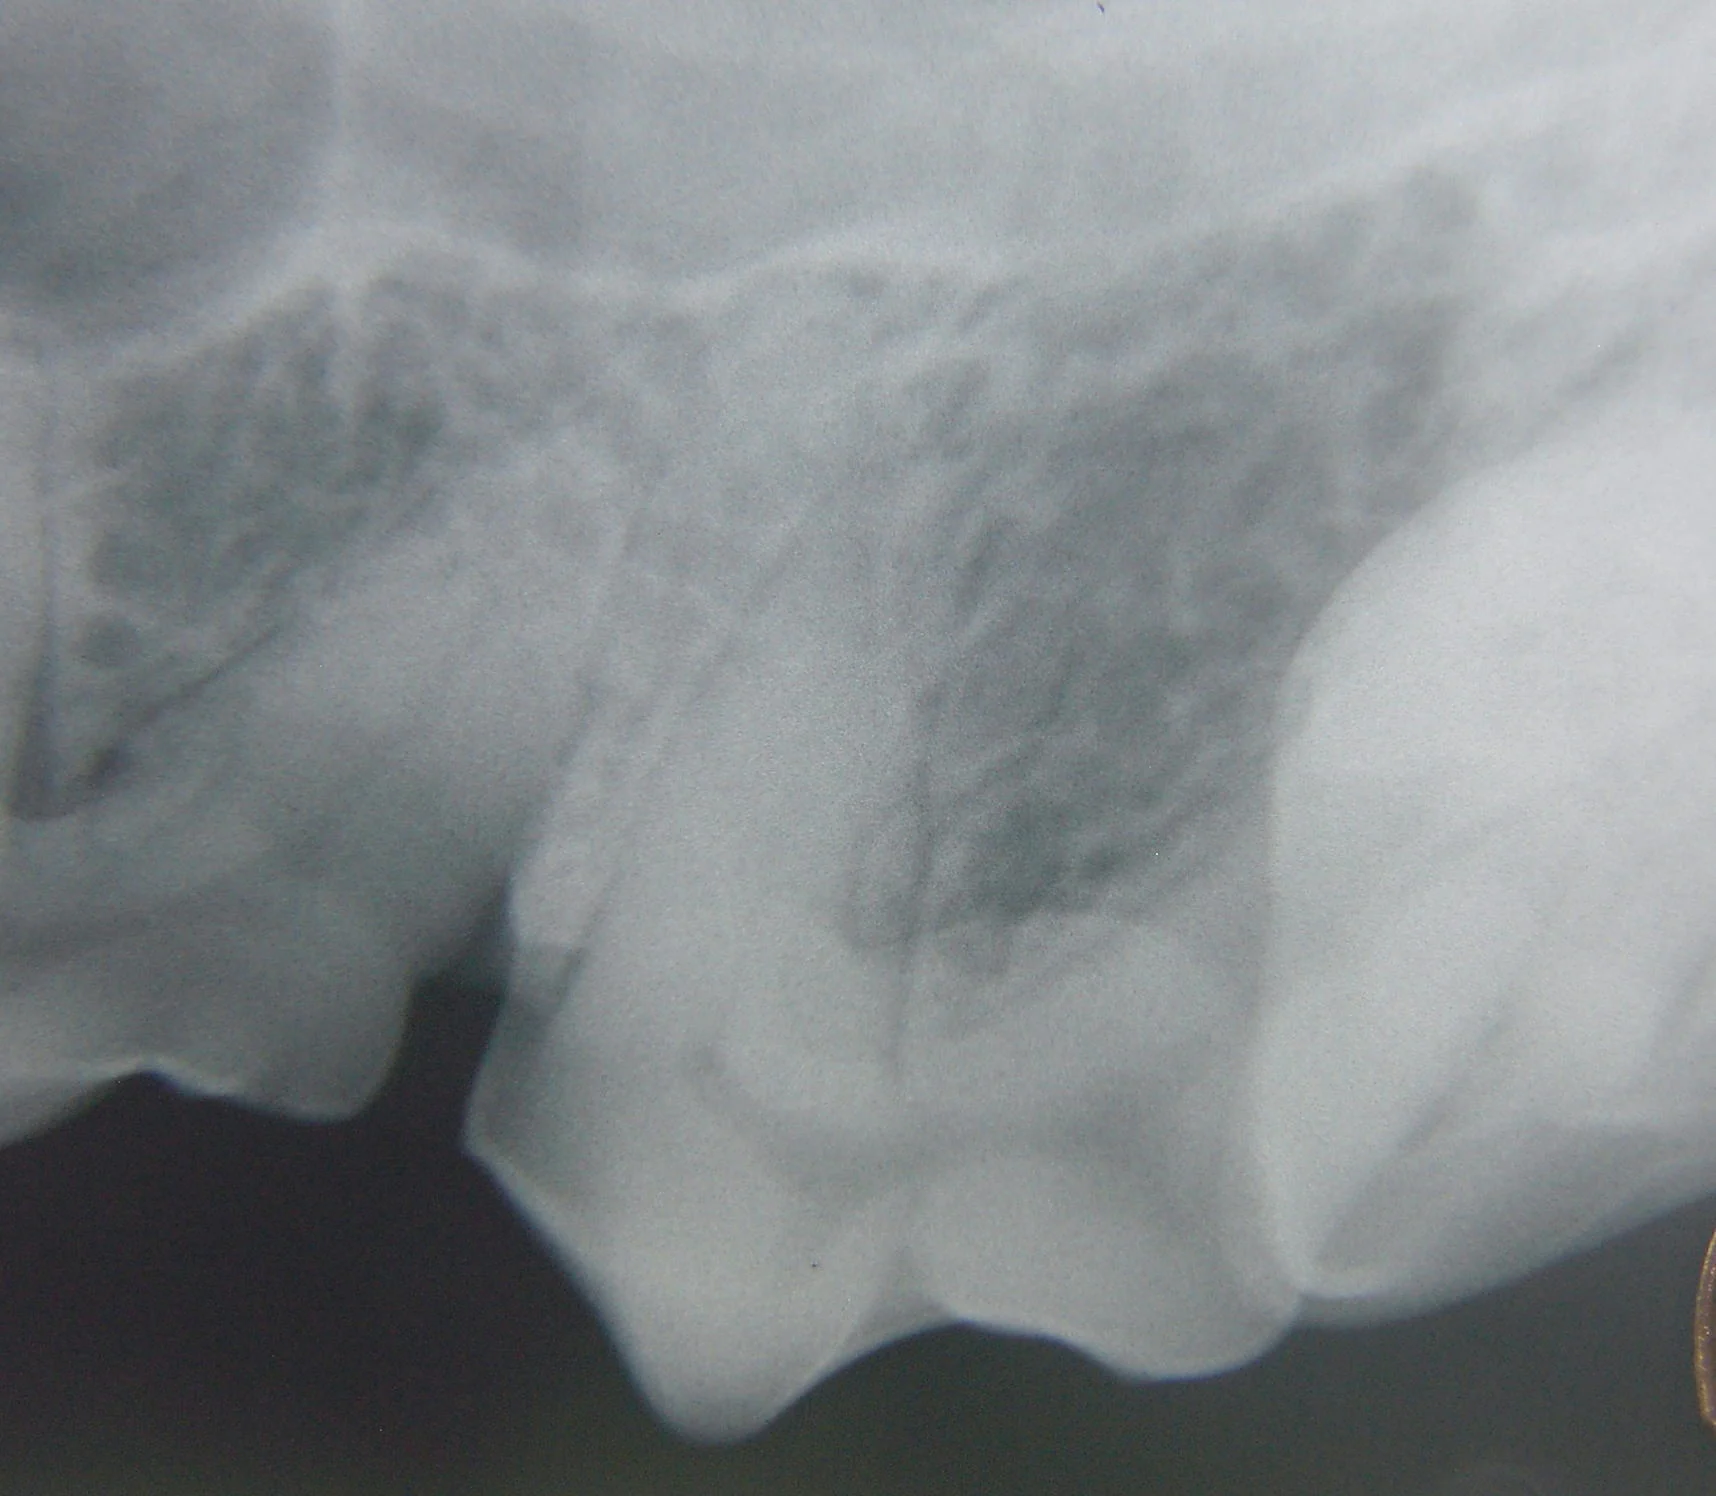

Step 4

Proper positioning of the x-ray machine tubehead (A). Again, it is not directed perpendicular to the long axis of the tooth or perpendicular to the plane of the film, but is instead placed halfway between these two reference alignments (B). This creates a good diagnostic image of the maxillary 4th premolar crown, roots, alveolar bone, and apexes of the roots (C). One limitation is the superimposition of the mesial roots on each other. The clinical significance of this superimposition is arguable.

For example, if periodontal bone loss is noted around one of the roots, periodontal probing should help to determine which root is involved. If periapical osteolysis is noted, then endodontic disease, which would affect all roots, is probably present. There may be instances where using radiographic techniques to separate the mesial roots may be helpful. If one of the roots were undergoing root resorption or ankylosis, this information may be valuable before extraction. Determination of the individual roots is also helpful when navigating the canals during initial assessment for root canal therapy or determination of root canal length.